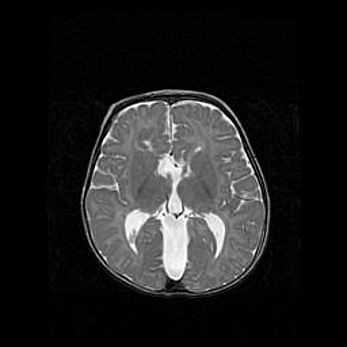

Множественные кисты обоих полушарий головного мозга, наибольшая из них в правой затылочной области. Ассиметричная атрофическая гидроцефалия.

Возраст: 7 месяцев

Вес: 5660 г

Пол: мужской

Окружность головы: 41,5 см

Срок гестации: 28-29 недель

Кисты головного мозга развиваются в результате многоочаговых некрозов вещества мозга и возникают вследствие перенесенной перинатальной инфекции, менингитов, энцефалитов, асфиксии, родовой травмы, расстройств мозгового кровообращения различного генеза. Образованию кист в веществе головного мозга плодов и новорожденных способствуют такие факторы, как высокое содержание в нем воды, недостаточная (или отсутствие) миелинизация и слабая астроглиальная реакция на повреждение.

Кисты могут сочетаться с гидроцефалией и другими поражениями головного мозга.